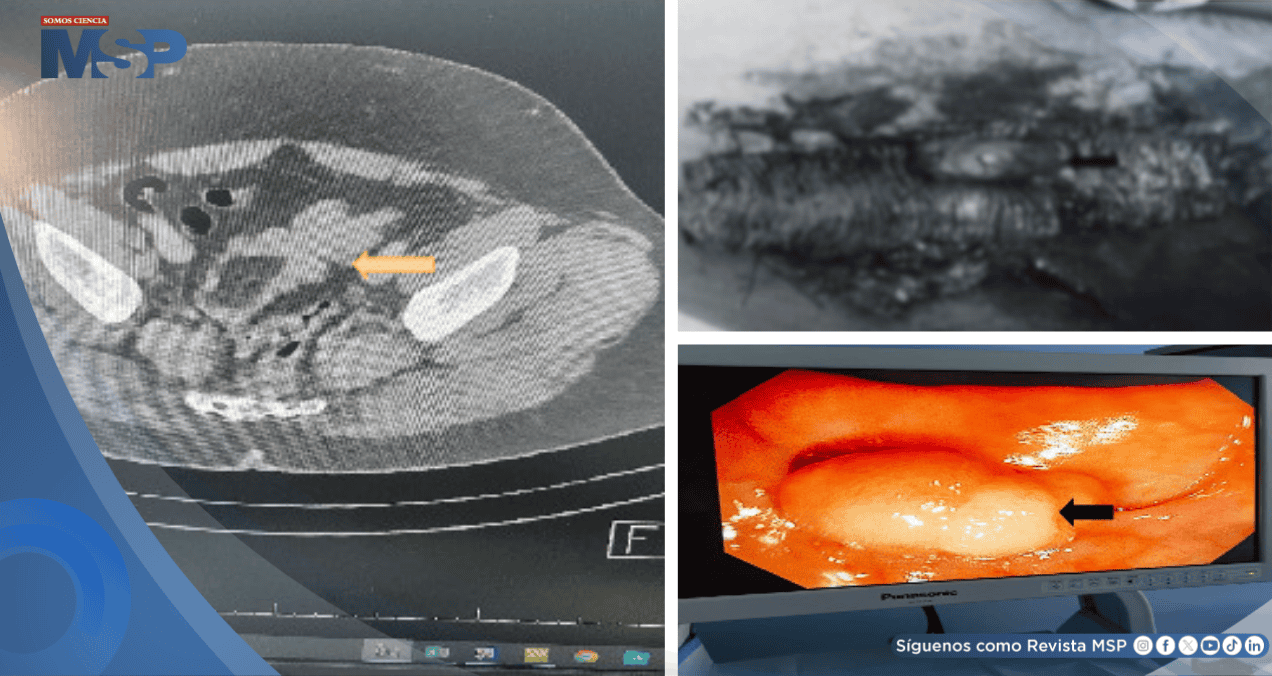

Se le realizaron exámenes de laboratorio, cuyos resultados estaban dentro de los límites normales. No se le realizó ecografía abdominal, pero sí se sometió a una tomografía computarizada a través de la cual se identificó una invaginación colo-colónica sigmoidea (condición en la que una sección del intestino grueso se dobla sobre sí misma, causando una obstrucción intestinal) con un punto de entrada.

La inflamación era 5 × 3,6 × 2,50 cm, con posibilidad de lipoma y, además, se realizó una colonoscopia que mostró una lesión pediculada blanquecina en el sigmoide que mide aproximadamente 3 × 5 cm.

La histopatología final mostró un cuadro morfológico sugestivo de lipoma (tumor benigno) con ulceración mucosa superpuesta, inflamación y formación de tejido de granulación, con ocho ganglios linfáticos reactivos y sin displasia ni malignidad en la muestra examinada.